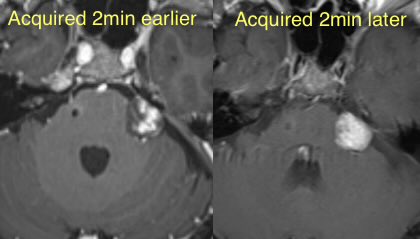

John Raseman

@daniel_gewolb Called a shrinking, enhancing extrusion that was misdiagnosed as a meningioma today thanks to you!

Daniel Gewolb, MD

▶️CHANTER syndrome is likely a diagnosis on the spectrum of opioid induced amnestic syndrome (which is isolated to the hippocampus) and pediatric opioid use-associated neurotoxicity w/ cerebellar edema (POUNCE)